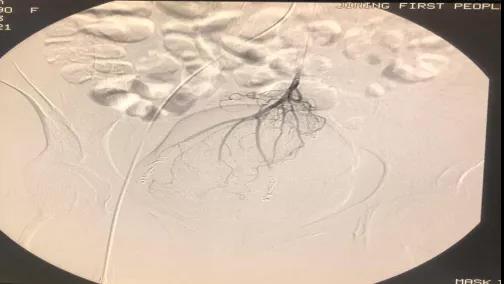

介入栓塞治疗前

介入栓塞治疗后

患者局麻下采用sedlinger技术穿刺股动脉(双侧都可以),送入导丝与导管,二者配合进行造影,找出双侧髂内动脉及肠系膜下动脉至直肠下端的痔疮供养动脉,造影证实无误后,透视下根据血管情况经导管引入弹簧圈及栓塞颗粒进行供血动脉栓塞,减少痔动脉血流,减轻直肠静脉丛压力,减轻症状,萎缩痔核。介入栓塞治疗后,患者疼痛与不适症状缓解,一般休息恢复2天~3天即可出院。